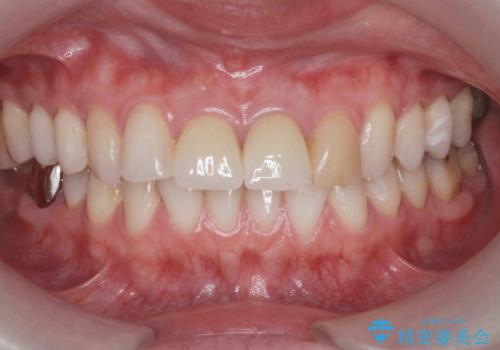

前歯の見た目を改善 セラミック審美治療

- 長年気になっている前歯の見た目を改善したいと来院されました。

両側の前歯に根尖性歯周炎を認めたため根管治療を行ったのち、ジルコニアクラウンを用いた審美性の改善を計画します。

前歯の見た目が改善したことで長年の悩みが解決できた。と治療内容に満足いただくことができました。